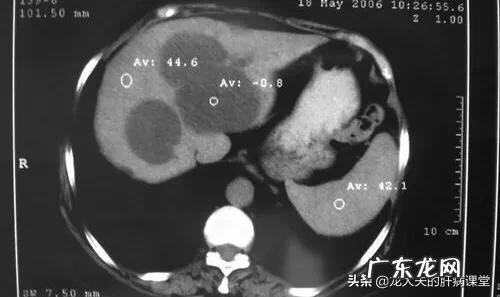

我们可以想象它是一个水泡 , 当水泡的出口和入口都封闭的时候 , 水泡里面的水出不去 , 水泡的壁越来越厚 。在B超或者CT上看到的囊肿 , 就是这个样子 , 囊肿里面由于是液体 , 密度会比周围的脏器要低一些 。

囊肿一般不生长或者生长非常缓慢 , 生长的原因主要是囊壁仍然有液体渗透进去 。所以 , 极少部分囊肿 , 由于越来越大 , 有可能会造成破裂 。这是囊肿最怕出现的情况 , 破裂后就有可能导致细菌感染 。

至于很多人担心肝囊肿会不会癌变的问题 , 目前没有证据表明肝囊肿会癌变 。有一小部分肝癌 , 一开始可能看起来像囊肿 , 那并不代表是由肝囊肿转变来的 , 而可能一开始就是比较罕见的小肝癌 。